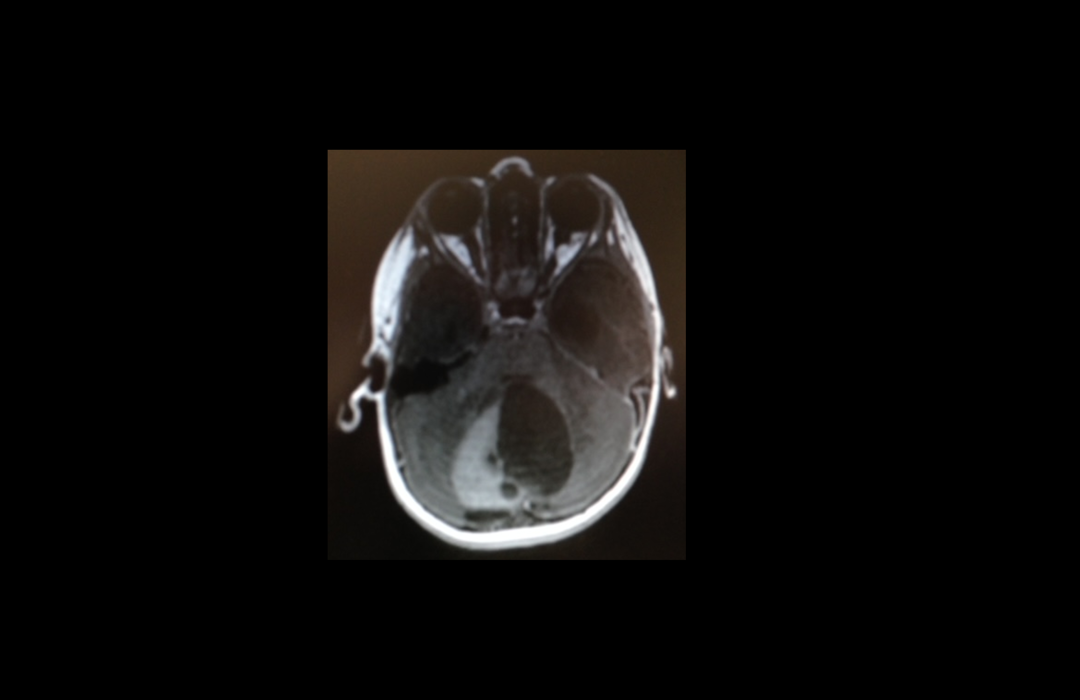

Den 16. marts 2015 blev hun indlagt, og der blev der slået i bordet. Lægen bemærkede, at My Josephines hovedomfang var lidt større end normal. Der blev foretaget en skanning i fuld narkose for at finde ud af, hvorfor hun var så dårlig. Beskeden fra lægerne var voldsom for My Josephines mor Rikke og hendes far. Der blev, til lægernes overraskelse, nemlig fundet en tumor i hendes lillehjerne. Og så gik det hele stærkt.

Hun blev ikke vækket af narkosen, men kørt direkte til Aarhus, hvor dygtige specialister straks opererede My Josephine, og fjernede tumoren i hendes lillehjerne.

Efter noget tid blev My Josephine overflyttet til børnekræftafdelingen i Aalborg. I ti lange dage ventede familien på at få besked om, hvilken grad af kræft, der var tale om. Det var en grad 2, der betød, at det var en såkaldt lavgradstumor. Lægerne havde fået fjernet hele tumoren, og der blev ikke givet kemoterapi.

En meget vellykket operation i lillehjernen betød herefter "kun" skanninger hver tredje måned de næste to år. Så blev skanningerne foretaget hvert halve år og i dag en gang om året.